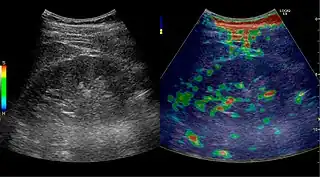

![]() Doppler ultrasound (US) of a normal adult kidney with the estimation of the systolic velocity (Vs), the diastolic velocity (Vd), acceleration time (AoAT), systolic acceleration (Ao Accel) and resistive index (RI). Red and blue colors in the color box represent flow towards and away from the transducer, respectively. The specrogram below the B-mode image shows flow velocity (m/s) against time (s) obtained within the range gate. The small flash icons on the spectrogram represent initiation of the flow measurement.[1] | |

Doppler ultrasonography of the kidney is widely used, and the vessels are easily depicted by the color Doppler technique in order to evaluate perfusion. Applying spectral Doppler to the renal artery and selected interlobular arteries, peak systolic velocities, resistive index, and acceleration curves can be estimated (Figure 4) (e.g., peak systolic velocity of the renal artery above 180 cm/s is a predictor of renal artery stenosis of more than 60%, and a resistive index, which is a calculated from peak systolic and end systolic velocity, above 0.70 is indicative of abnormal renovascular resistance).[1]